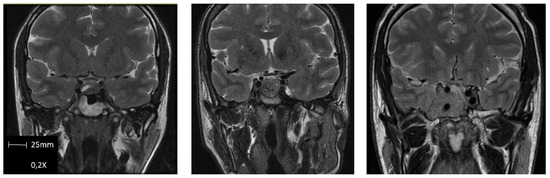

| T2-weighted M.R.I. intensity n, (%) | |

| Hypointense | 4 (9.1) |

| Isointense | 21 (47.7) |

| Hyperintense | 19 (43.2) |

| MRI T2-weighted intensity | Hyperintensity | Long-term remission | 0.091 (0.017–0.494) | 0.045 |

| Recurrence | 13.444 (2.470–73.192) | 0.001 | ||

| Reintervention | 1.941 (1.291–12.950) | 0.046 | ||

| MRI T2-weighted intensity | Hyperintensity | Recurrence | 8.704 (4.800–14.350) | 0.026 |

| Reintervention | 1.145 (1.032–2.445) | 0.03 | ||